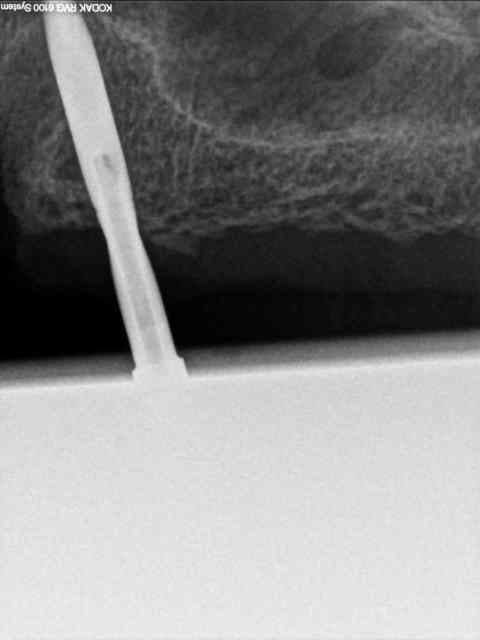

secteur 2:

on voit bien ici que cette méthode reste suffisamment précise pour longer le sinus sans le pénétrer.

je n'en demande pas d'avantage.

Cet implant pénètre de 5 à 6 mm dans le sinus.